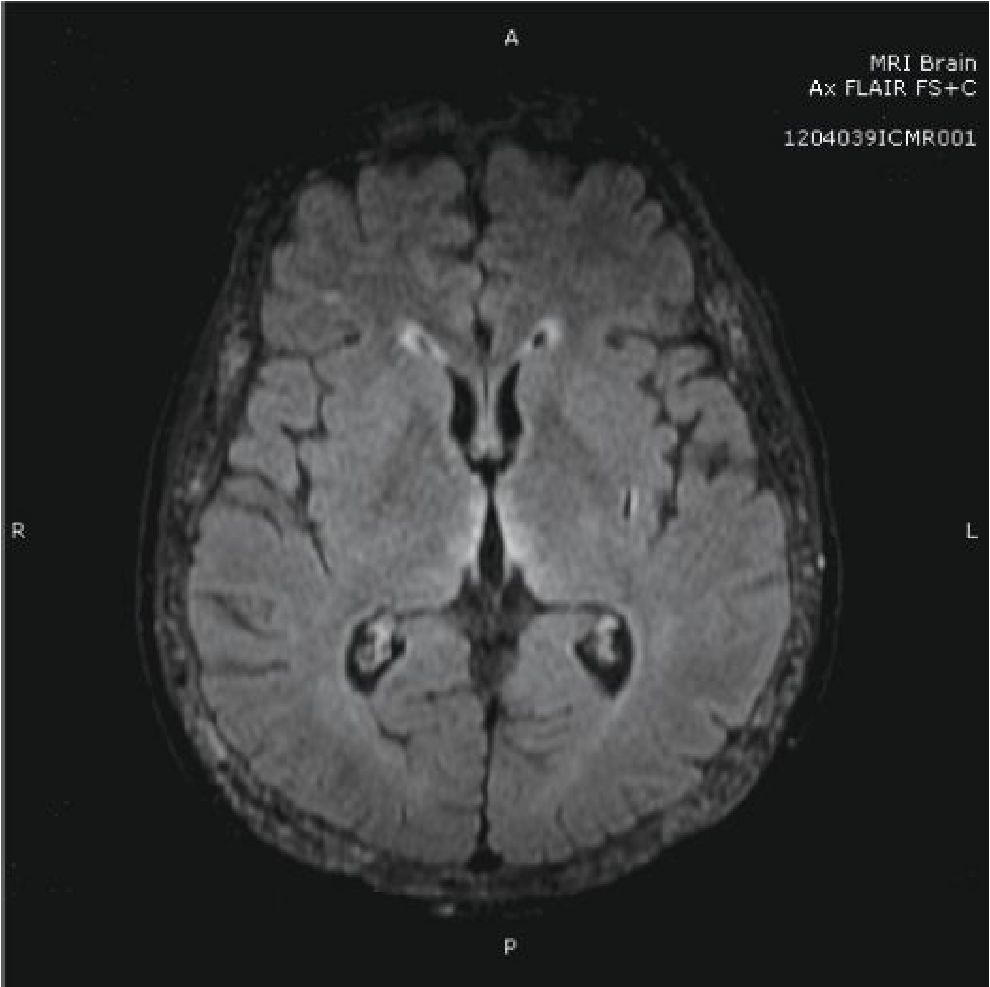

A 51-year-old female with ESRD of unknown etiology received deceased donor KT from a 57-year-old donor. The cold ischemic time was 22 hours. The degree of HLA mismatch was 2 of 6 and the recipient PRA was 3%. The dialysis vintage was 8 years. The immunosuppression included basiliximab induction, tacrolimus, mycophenolate mofetil (MMF) and prednisolone. She had delayed graft function (DGF) requiring hemodialysis for 3 weeks. On 4th week, the kidney function was improved. Urine output increased to about 1000-3000 ml per day and serum creatinine was 2.17 mg/dl. Transplant kidney biopsy at 6th week showed acute tubular necrosis without evidence of rejection. Two months after KT she presented with the change of mental status for a few days. She subsequently had psychomotor retardation, slow speech, myoclonus on both hands followed by generalized tonic-clonic seizure. Antiepileptic drugs were administrated by phenytoin and diazepam intravenously. Serum electrolyte was normal, the platelet count was 48,000 /ml, hemoglobin 10.9 g/dl and peripheral blood smear show schistocyte, polychromasia, and decrease platelet compatible with microangiopathic hemolytic anemia (MAHA) pattern. Tacrolimus level was 6.0 ng/ml. MRI brain showed multifocal symmetric hypersignal FLAIR lesion at bilateral medial thalami, bilateral hypothalami, bilateral optic tract, bilateral periventricular frontal horns and subcortical area compatible with posterior reversible encephalopathy syndrome (PRES) [figure 1]. Serum creatinine rose to 6.49 mg/dL, blood urea nitrogen (BUN) was 65 mg/dL and donor-specific antibody is negative. The diagnosis of TTP/HUS was given. Plasmapheresis was initiated accompany with hemodialysis. Tacrolimus was stopped. Repeated kidney biopsy showed fibrin thrombi, shrinkage of the glomerular tufts, without crescent. The arteries show endothelial swelling with foamy cells and focal intimal arteritis, arterioles show moderate hyaline and fibrin thrombi. The findings are compatible with thrombotic microangiopathy [figure 2]. The peritubular capillaries (PTC) show focal luminal leukocytes (less than 10% of cortical PTC) and the immunop-eroxidase staining for C4d is focally positive (10%). Several weeks after treatments, the neurological symptoms improved, TMA was in remission but required regular hemodialysis.

Figure 1 MRI brain showed multifocal symmetric hypersignal FLAIR lesion at bilateral medial thalami, bilateral hypothalami, bilateral optic tract, bilateral periventricular frontal horns and subcortical area